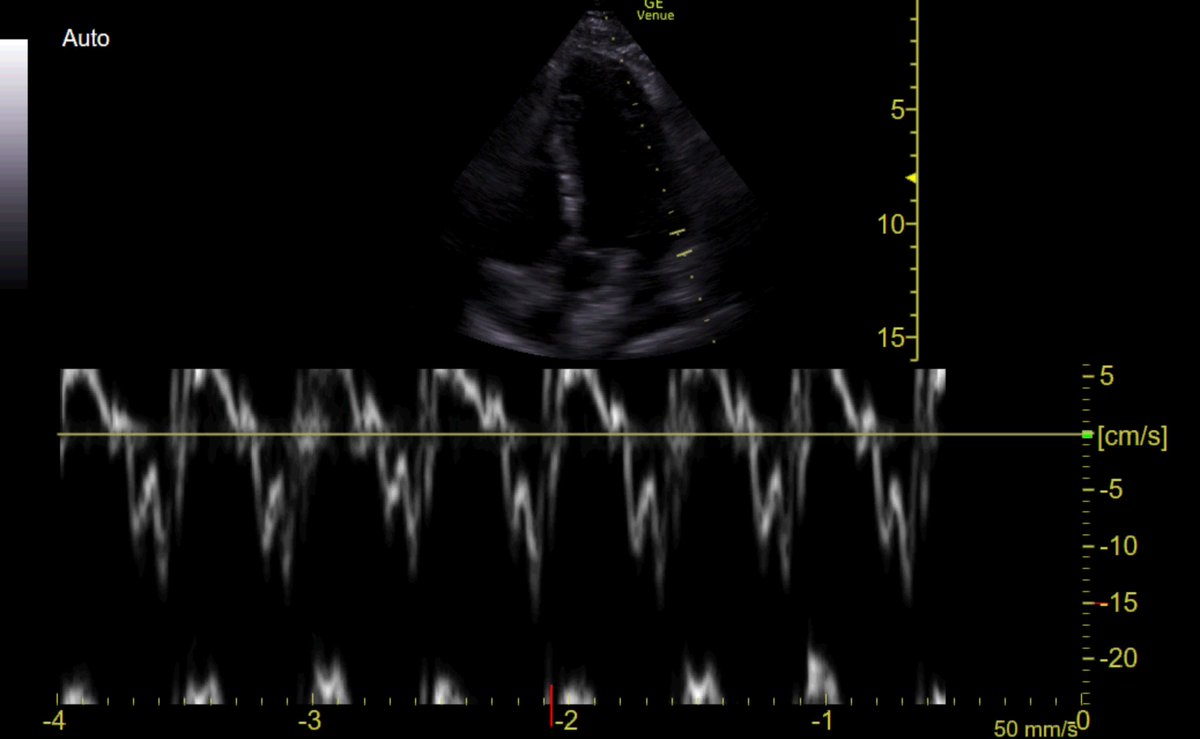

#POCUS ➡️large IVC (2.8 cm)

Plethoric IVC is likely due to IMV, this patient has low preload!

⬇️ preload can be caused by sepsis (venodilation/3rd spacing) or hypovolemia

#EchoFirst can't distinguish between these!

So, before giving fluid, it is wise to look for fluid tolerance 👇